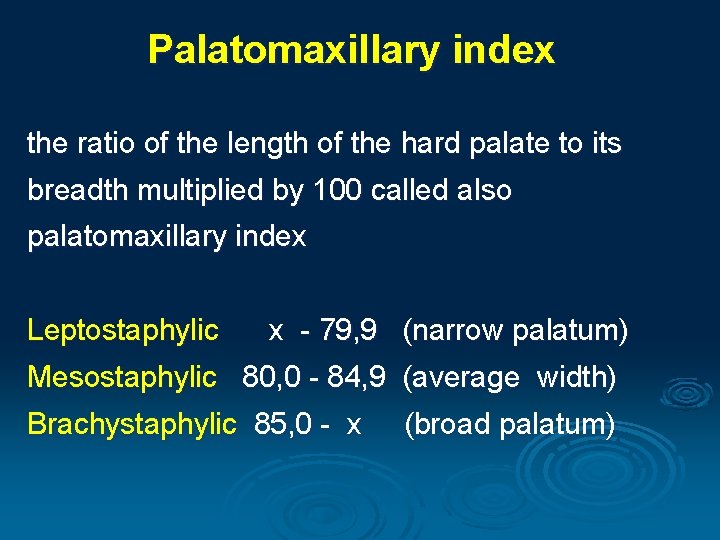

Palatomaxillary index the ratio of the length of the hard palate to its breadth multiplied by 100 called also palatomaxillary index Leptostaphylic x - 79, 9 (narrow palatum) Mesostaphylic 80, 0 - 84, 9 (average width) Brachystaphylic 85, 0 - x (broad palatum)